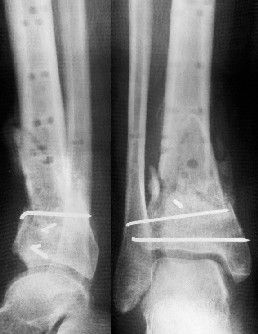

Уважаемые коллеги!Поступила пациентка 40лет, псевдоартроз Н/3 большеберцовой кости, оперирована 1,5-а года назад по поводу перелома ПИЛОНА в Австрии, травма горнолыжная.

после остеосиннтеза |  05.07.04 |  12.04.05 | Пластина удалена через 4-е месяца (миграция винтов), полимерная повязка на 2-а мес. Беспокоит деформация голени,укорочение 1-1,5см, боли незначительные, движения в г/стопном суставе в полном объёме, ходит с полной нагрузкой на ногу, подвижность в переломе не определяется. Одномоментное исправление деформации, костная пластика (chronOS)+ пластина? Аппаратная коррекция, затем пластина? Аппарат? Прошу Ваших советов. С Уважением А.Миронов